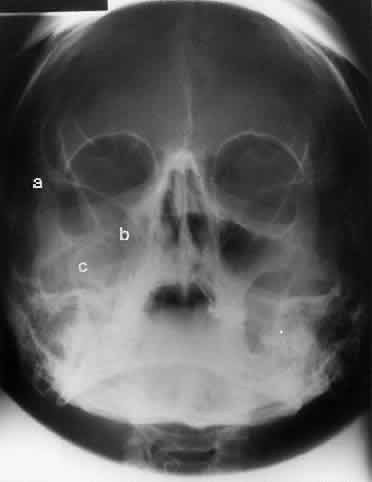

CALDWELL PROJECTION

In 1918 the evaluation of the frontal and ethmoid sinuses prompted Caldwell9 to describe a projection (Fig. 3) that eliminates the superimposition of the sphenoid bone on these paranasal sinuses. The patient is positioned with both the nose and forehead against the x-ray cassette while the x-ray beam is directed downward 15 degrees to 23 degrees to the canthomeatal line.5,6,9 This orientation also projects the petrous bones inferior to the orbit, thus avoiding obscuration of the orbital structures. As in the Waters view, the Caldwell view is a posterior-anterior projection. This excellent view of the frontal and ethmoid sinuses also allows good visualization of the orbital rims, greater and lesser sphenoid wings, lacrimal gland fossa, medial orbital wall, and both the superior and inferior orbital fissures.10 The innominate line is prominent in this view and represents the depression on the temporal surface of the greater wing of the sphenoid bone where it forms the medial wall of the temporal fossa or lateral wall of the orbit. This innominate line can be straight, end with a medial right angle turn, or continue inferiorly to form the outline of the pterygoid plate.8 A lack of continuity of the innominate line suggests a fracture of the lateral orbital wall.

Fig. 3. A. Schematic showing positioning for a Caldwell projection. (CM, canthomeatal line; CR, central ray) B. Radiograph of a Caldwell projection. The petrous ridge is positioned at the orbital floor. Detail of the orbital floor and maxillary sinus is blocked. C. The radiograph is taken at a steeper angle so the petrous ridge is now positioned lower within the maxillary antrum. (a, frontal sinus; b, innominate line; c, inferior orbital rim; d, posterior orbital floor; e, superior orbital fissure; f, greater wing of sphenoid;g, ethmoid sinus; h, medial orbital wall; i, petrous ridge; j, zygomatic-frontal suture; k, foramen rotundum) (A; Rao VM, Gonzalez CF: Plain film radiography and polytomography of the orbit. In Gonzalez CF, Becker MH, Flanagan JC [eds]: Diagnostic Imaging in Ophthalmology, pp 1–7. New York, Springer Verlag, 1986)

The posterior segment of the lateral wall courses posterior medially and can be seen in anterior projections such as the Caldwell view. This view allows direct visualization of the greater sphenoid wing contribution to the lateral wall. Bone density changes in the greater wing of the sphenoid, such as from a meningioma, can be detected. Fractures of the lateral orbital wall can occur from blunt trauma to the malar prominence. The zygomatic complex fracture (tripod) results from separation of the zygomatic-frontal, zygomatic-temporal, and the zygomatic-maxillary sutures. These fractures are associated with an inferior displacement of the malar prominence and a rounded lateral canthus (Figs. 8 and 9).

Fig. 8. A zygomatic complex fracture (tripod) after blunt trauma to the right cheek. Note the right zygoma is inferiorly displaced. (a, zygomatic-frontal suture separation; b, orbital rim disruption; c, opacification of maxillary sinus)

Fig. 9. Bilateral zygomatic complex and LeFort II fracture after reduction using fixation plates. Caldwell projection shows good alignment of orbital margin and zygomatic bones.